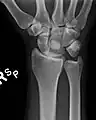

The lunate bone (semilunar bone) is a carpal bone in the human hand. It is distinguished by its deep concavity and crescentic outline. It is situated in the center of the proximal row carpal bones, which lie between the ulna and radius and the hand. The lunate carpal bone is situated between the lateral scaphoid bone and medial triquetral bone.

The lunate is a crescent-shaped carpal bone found within the hand. The lunate is found within the proximal row of carpal bones. Proximally, it abuts the radius. Laterally, it articulates with the scaphoid bone, medially with the triquetral bone, and distally with the capitate bone. The lunate also articulates on its distal and medial surface with the hamate bone.[2]: 708 [3]

The proximal surface of the lunate bone is smooth and convex, articulating with the radius. The lateral surface is flat and narrow, with a crescentic facet for articulation with the scaphoid bone. The medial surface possesses a smooth and quadrilateral facet for articulation with the triquetral bone. The palmar surface is rough, as is the dorsal surface. The dorsal surface is broad and rounded. The distal surface of the bone is deep and concave.[4]